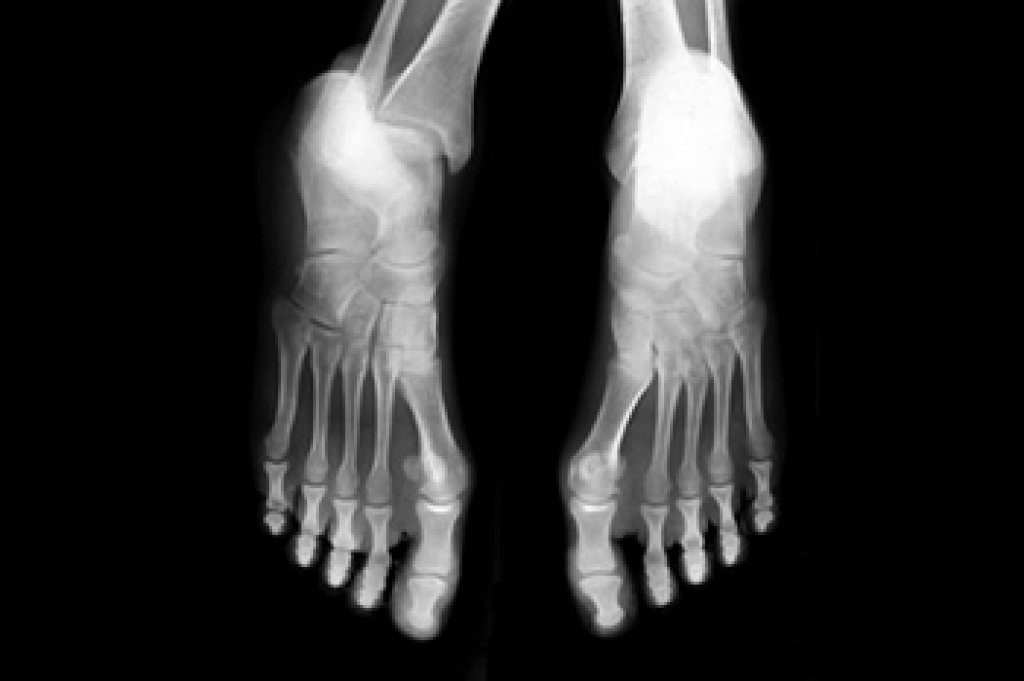

Doctors often perform two tests – blood tests and x-rays – when trying to diagnose bunions, especially in the early stages of development. Blood tests help determine if the foot pain is being caused by something else, such as arthritis, while x-rays provide a clear picture of your bone structure to your doctor.